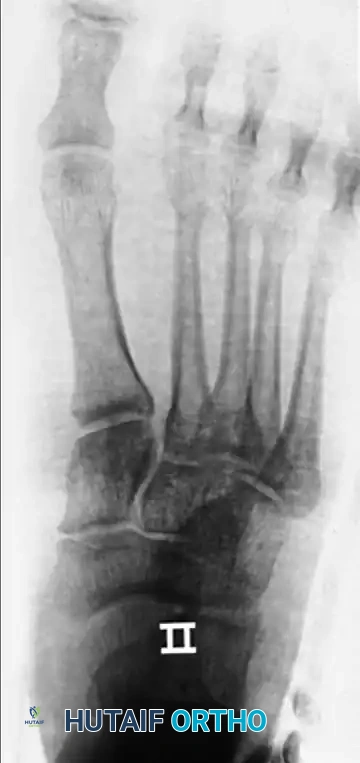

Radiographic Assessment

Standard weight-bearing (if tolerated) anteroposterior (AP), lateral, and oblique radiographs of the foot are mandatory. The lateral view will clearly demonstrate the dorsal displacement of the proximal phalanx. The AP view is critical for assessing the sesamoid complex to apply the Jahss classification.

Radiographic examples demonstrating complex dislocation patterns of the first ray. Note the displacement of the sesamoid complex which dictates the Jahss classification and subsequent reducibility.